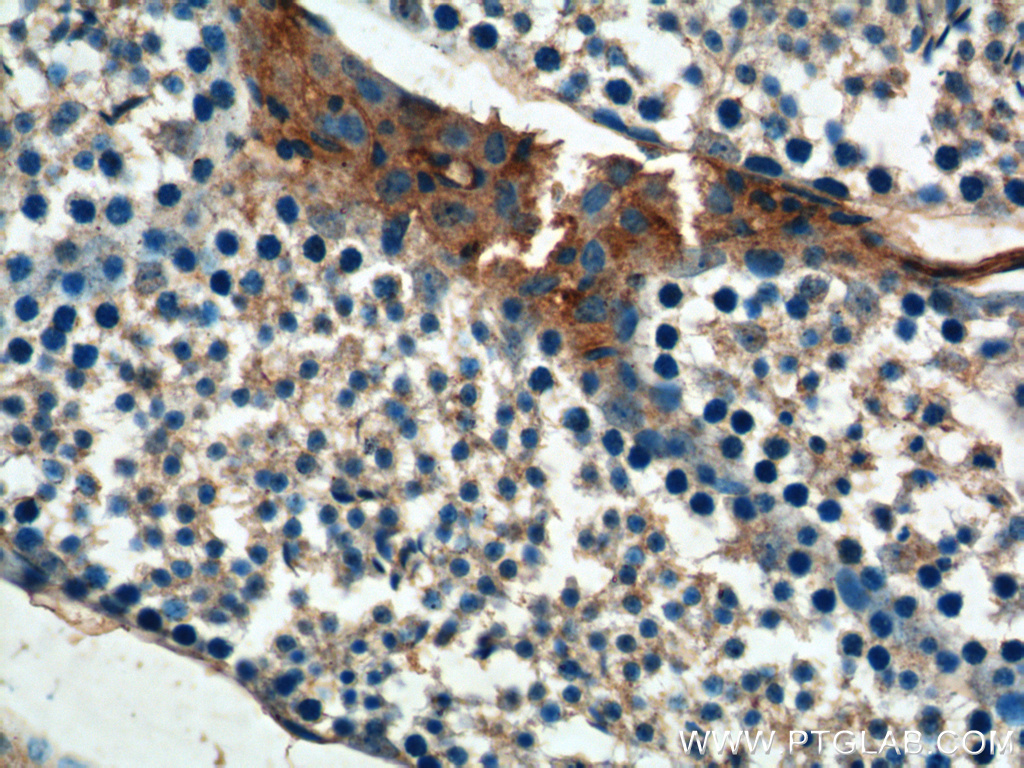

| Positive IHC detected in | human prostate hyperplasia tissue, mouse testis tissue, human stomach cancer tissue Note: suggested antigen retrieval with TE buffer pH 9.0; (*) Alternatively, antigen retrieval may be performed with citrate buffer pH 6.0 |

| Immunohistochemistry (IHC) | IHC : 1:50-1:500 |